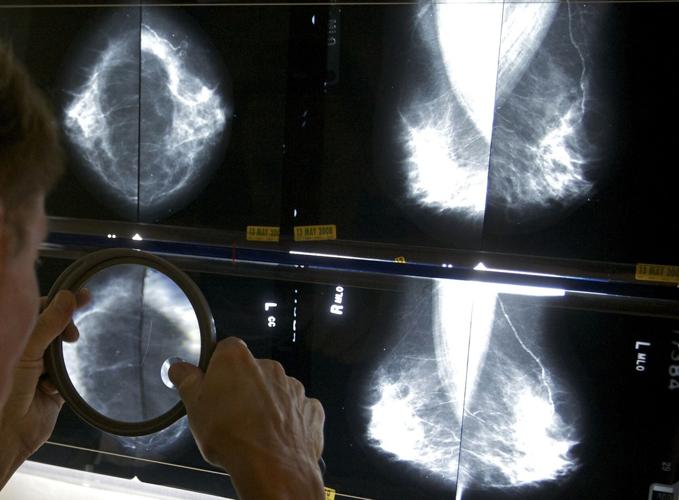

FILE - A radiologist uses a magnifying glass to check mammograms for breast cancer in Los Angeles, May 6, 2010. (AP Photo/Damian Dovarganes, File)